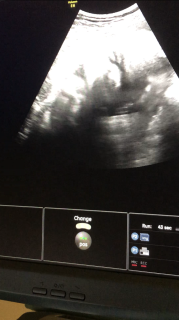

写真:37w4d:ゆうママさん:2900g

2900gの女の子です。 内診でだいぶん下がってきたねーと言われましたがなかなか子宮口が開いておらず。 散歩等の日々です(笑) 早く会いたいよぉ~お姫様。 顔はパパ似かな??笑

37w4dで、2400g

38w4dで、2680g

エコーは37wのときのです♪